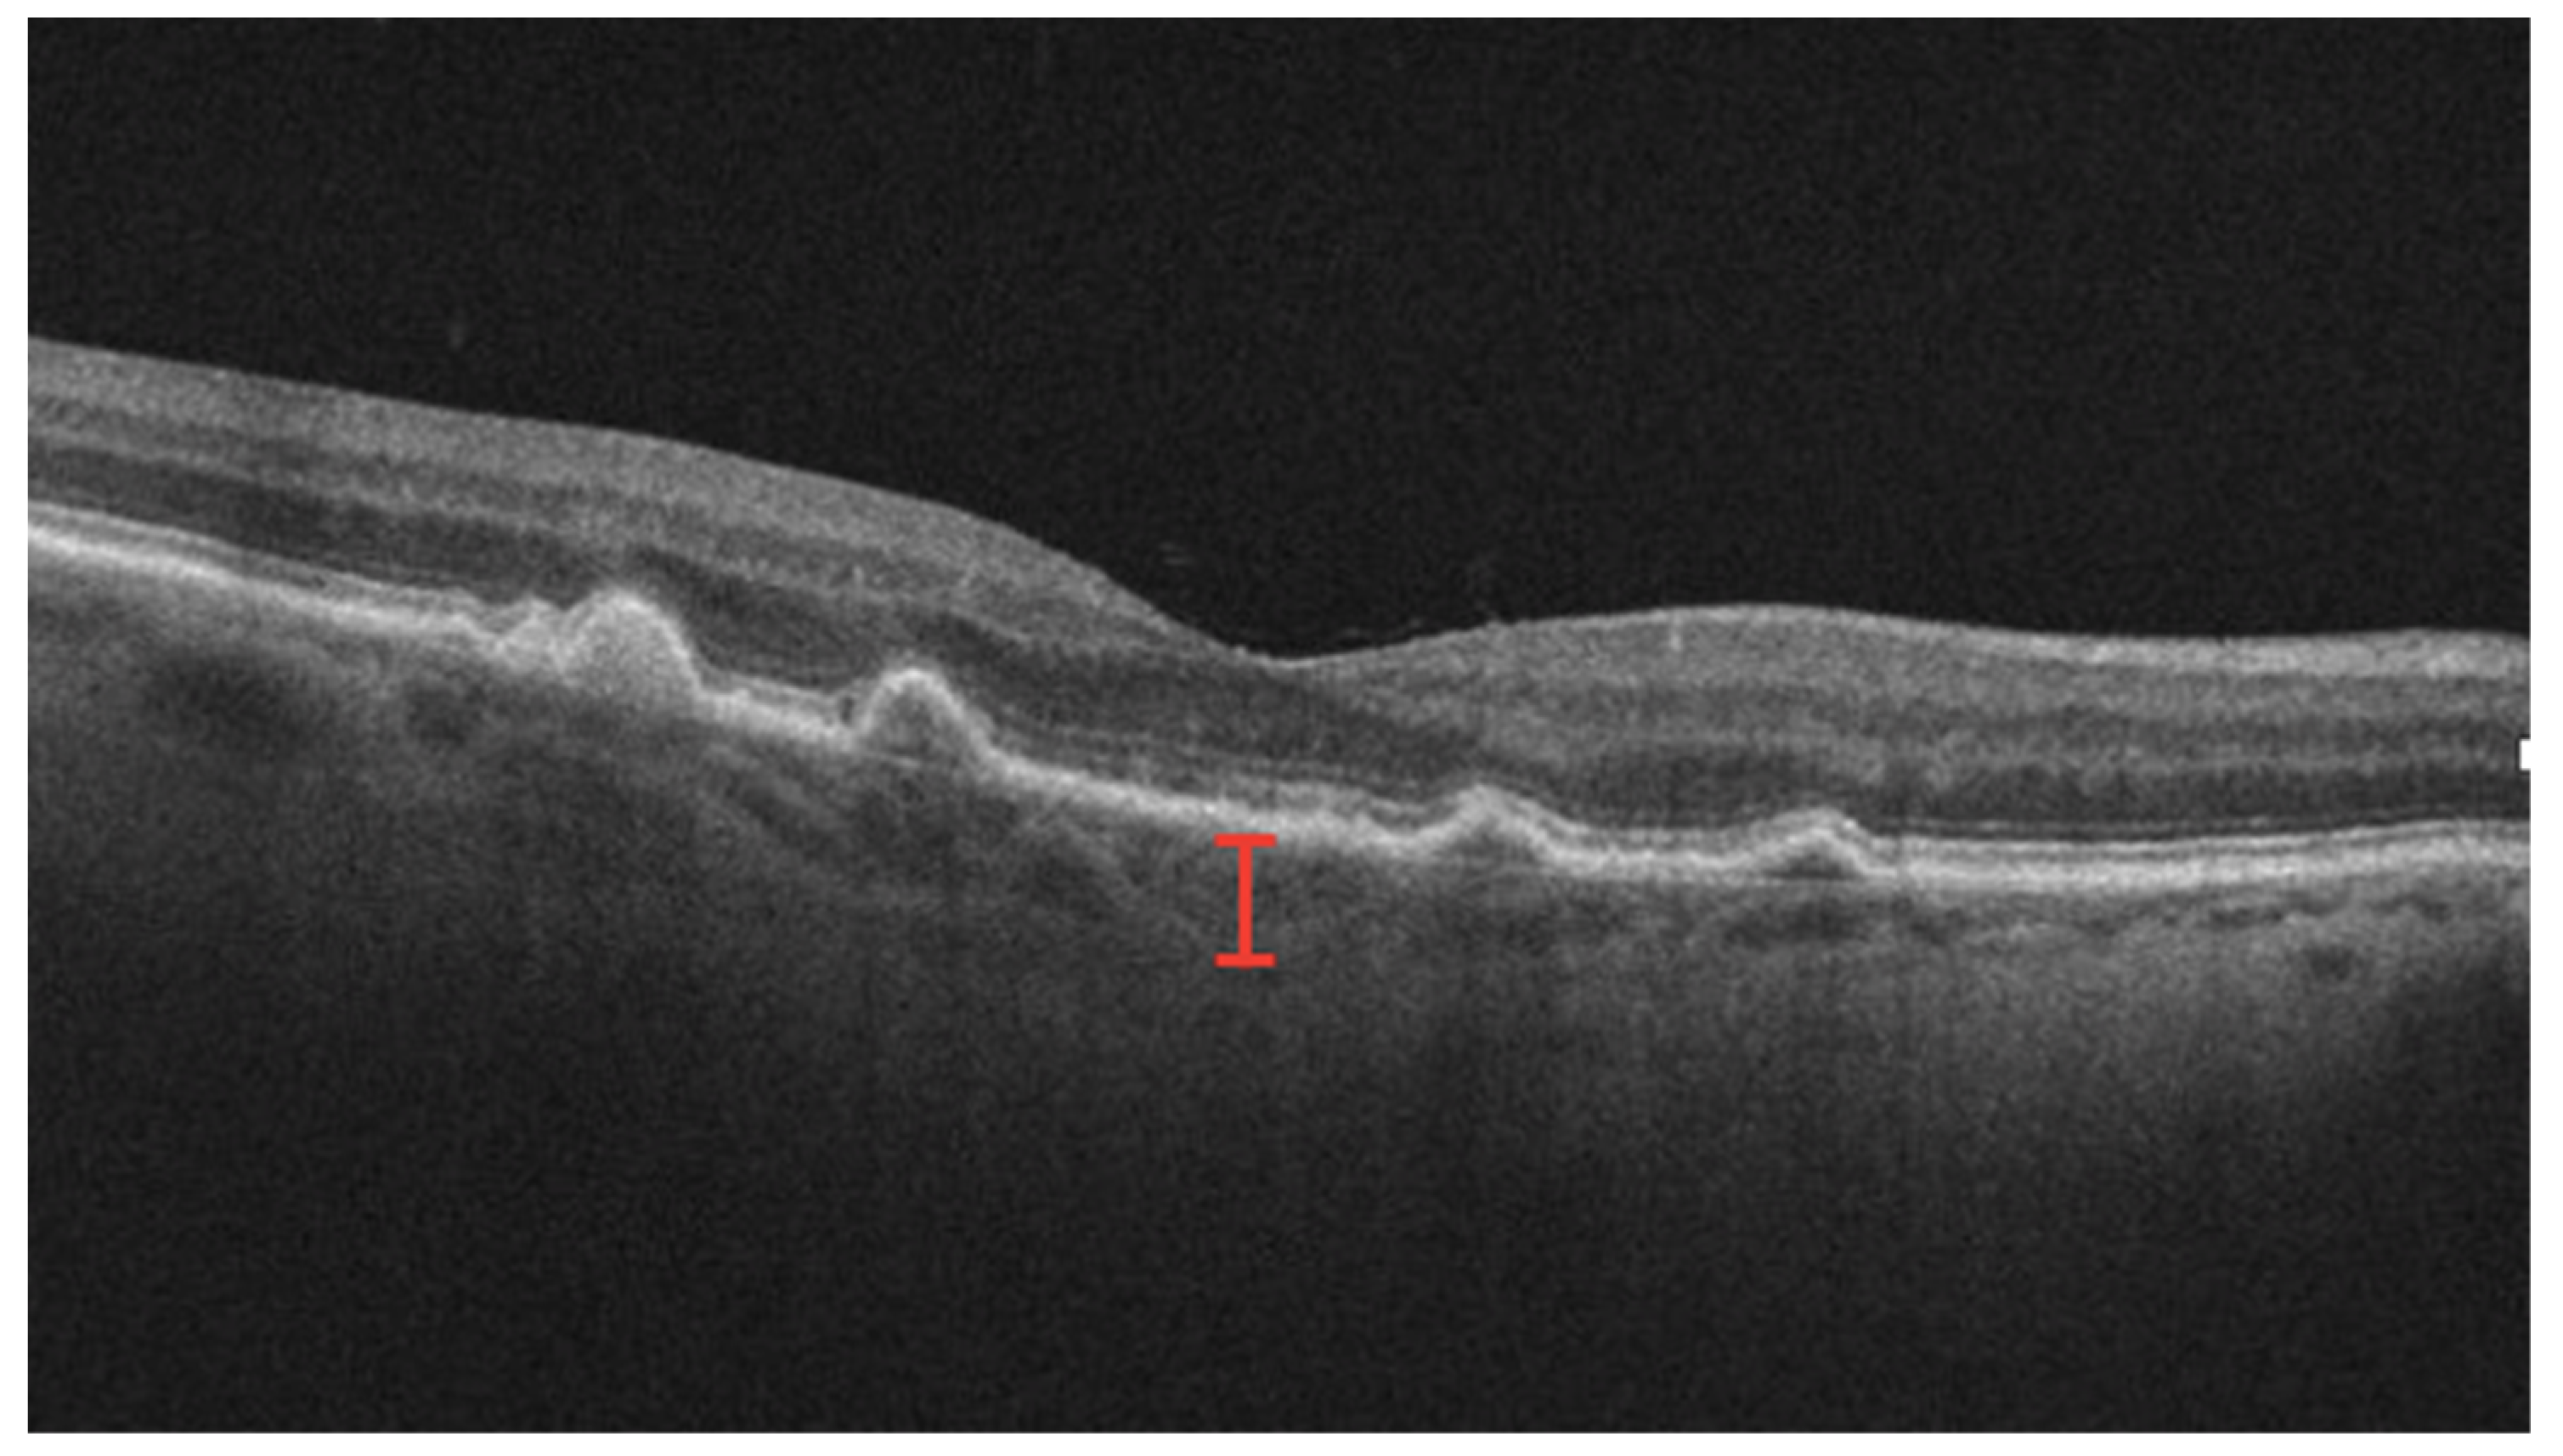

3.7. RPE Rips

- Chiang, A.; Chang, L.K.; Yu, F.; Sarraf, D. Predictors of anti-VEGF-associated retinal pigment epithelial tear using FA and OCT analysis. Retina 2008, 28, 1265–1269. [Google Scholar] [CrossRef] [PubMed]

- Chan, C.K.; Abraham, P.; Meyer, C.H.; Kokame, G.T.; Kaiser, P.K.; Rauser, M.E.; Gross, J.G.; Nuthi, A.S.; Lin, S.G.; Daher, N.S. Optical coherence tomography-measured pigment epithelial detachment height as a predictor for retinal pigment epithelial tears associated with intravitreal bevacizumab injections. Retina 2010, 30, 203–211. [Google Scholar] [CrossRef]

- Sastre-Ibáñez, M.; Martínez-Rubio, C.; Molina-Pallete, R.; Martínez-López-Corell, P.; Wu, L.; Arévalo, J.F.; Gallego-Pinazo, R. Retinal pigment epithelial tears. J. Fr. Ophtalmol. 2018, 42, 63–72. [Google Scholar] [CrossRef]

- Shiraki, K.; Kohno, T.; Ataka, S.; Abe, K.; Inoue, K.; Miki, T. Thinning and small holes at an impending tear of a retinal pigment epithelial detachment. Graefe’s Arch. Clin. Exp. Ophthalmol. 2001, 239, 430–436. [Google Scholar] [CrossRef] [PubMed]